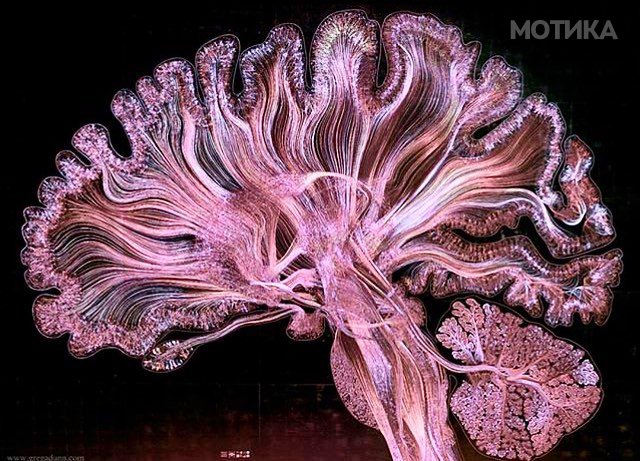

4. Трактографија (специјален МР метод) покажува нервни влакна кои ги поврзуваат различните делови на мозокот